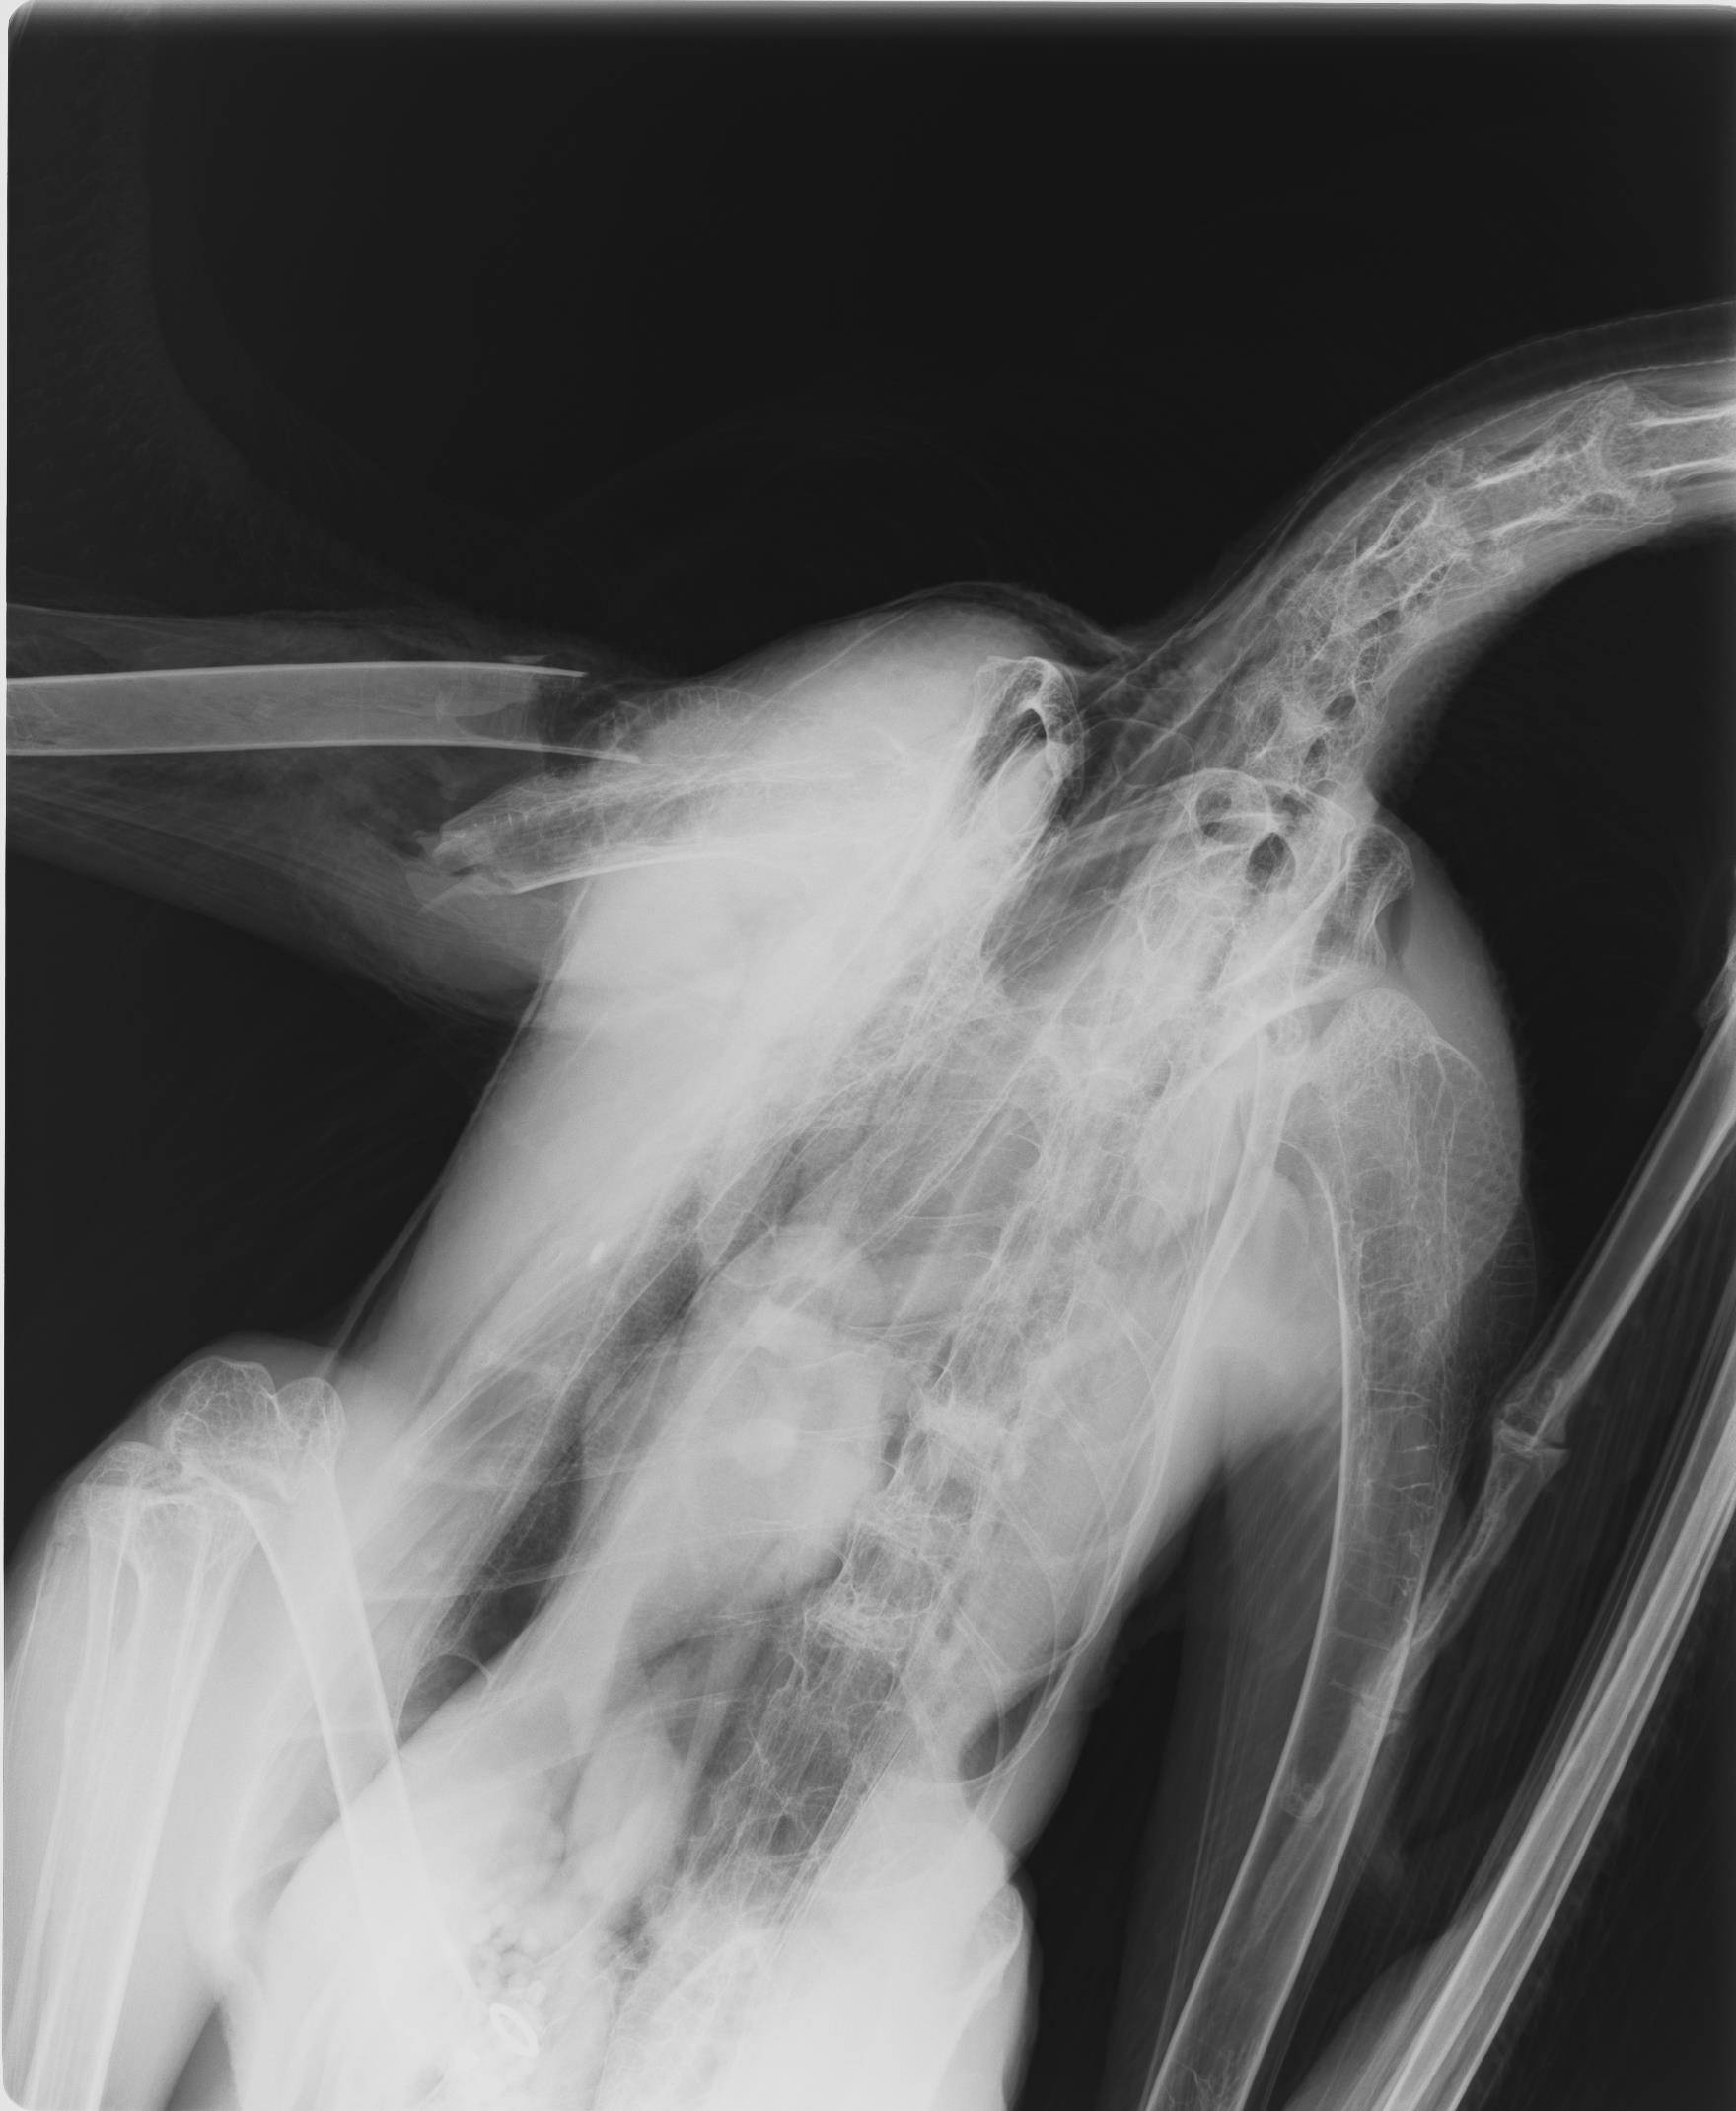

麻酔をかけてレントゲンで状態を確認すると、上腕骨の肩関節の近くで折れていました。

幸い、骨は体内から飛び出しておらず非開放の綺麗な状態でしたので、そのまま骨折の手術を行いました。医療用のピンを使い、骨が元々あった通りに整復しました。